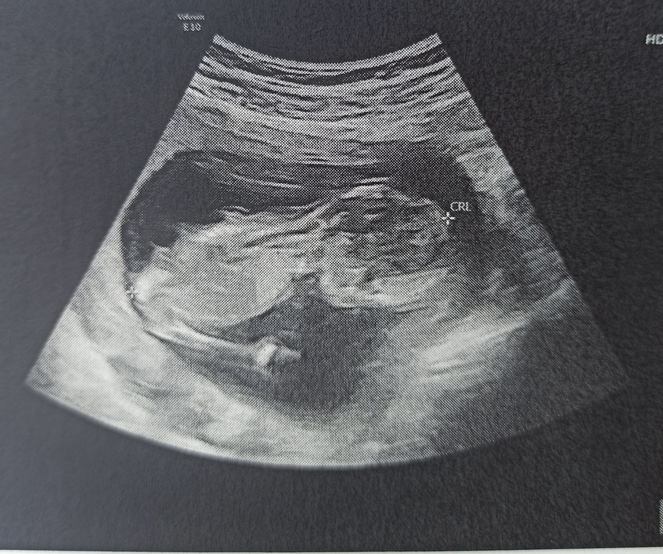

Wohin mit uns? - Tagebücher aus der Schwangerschaft von Clementine aus Valencia - Spanien